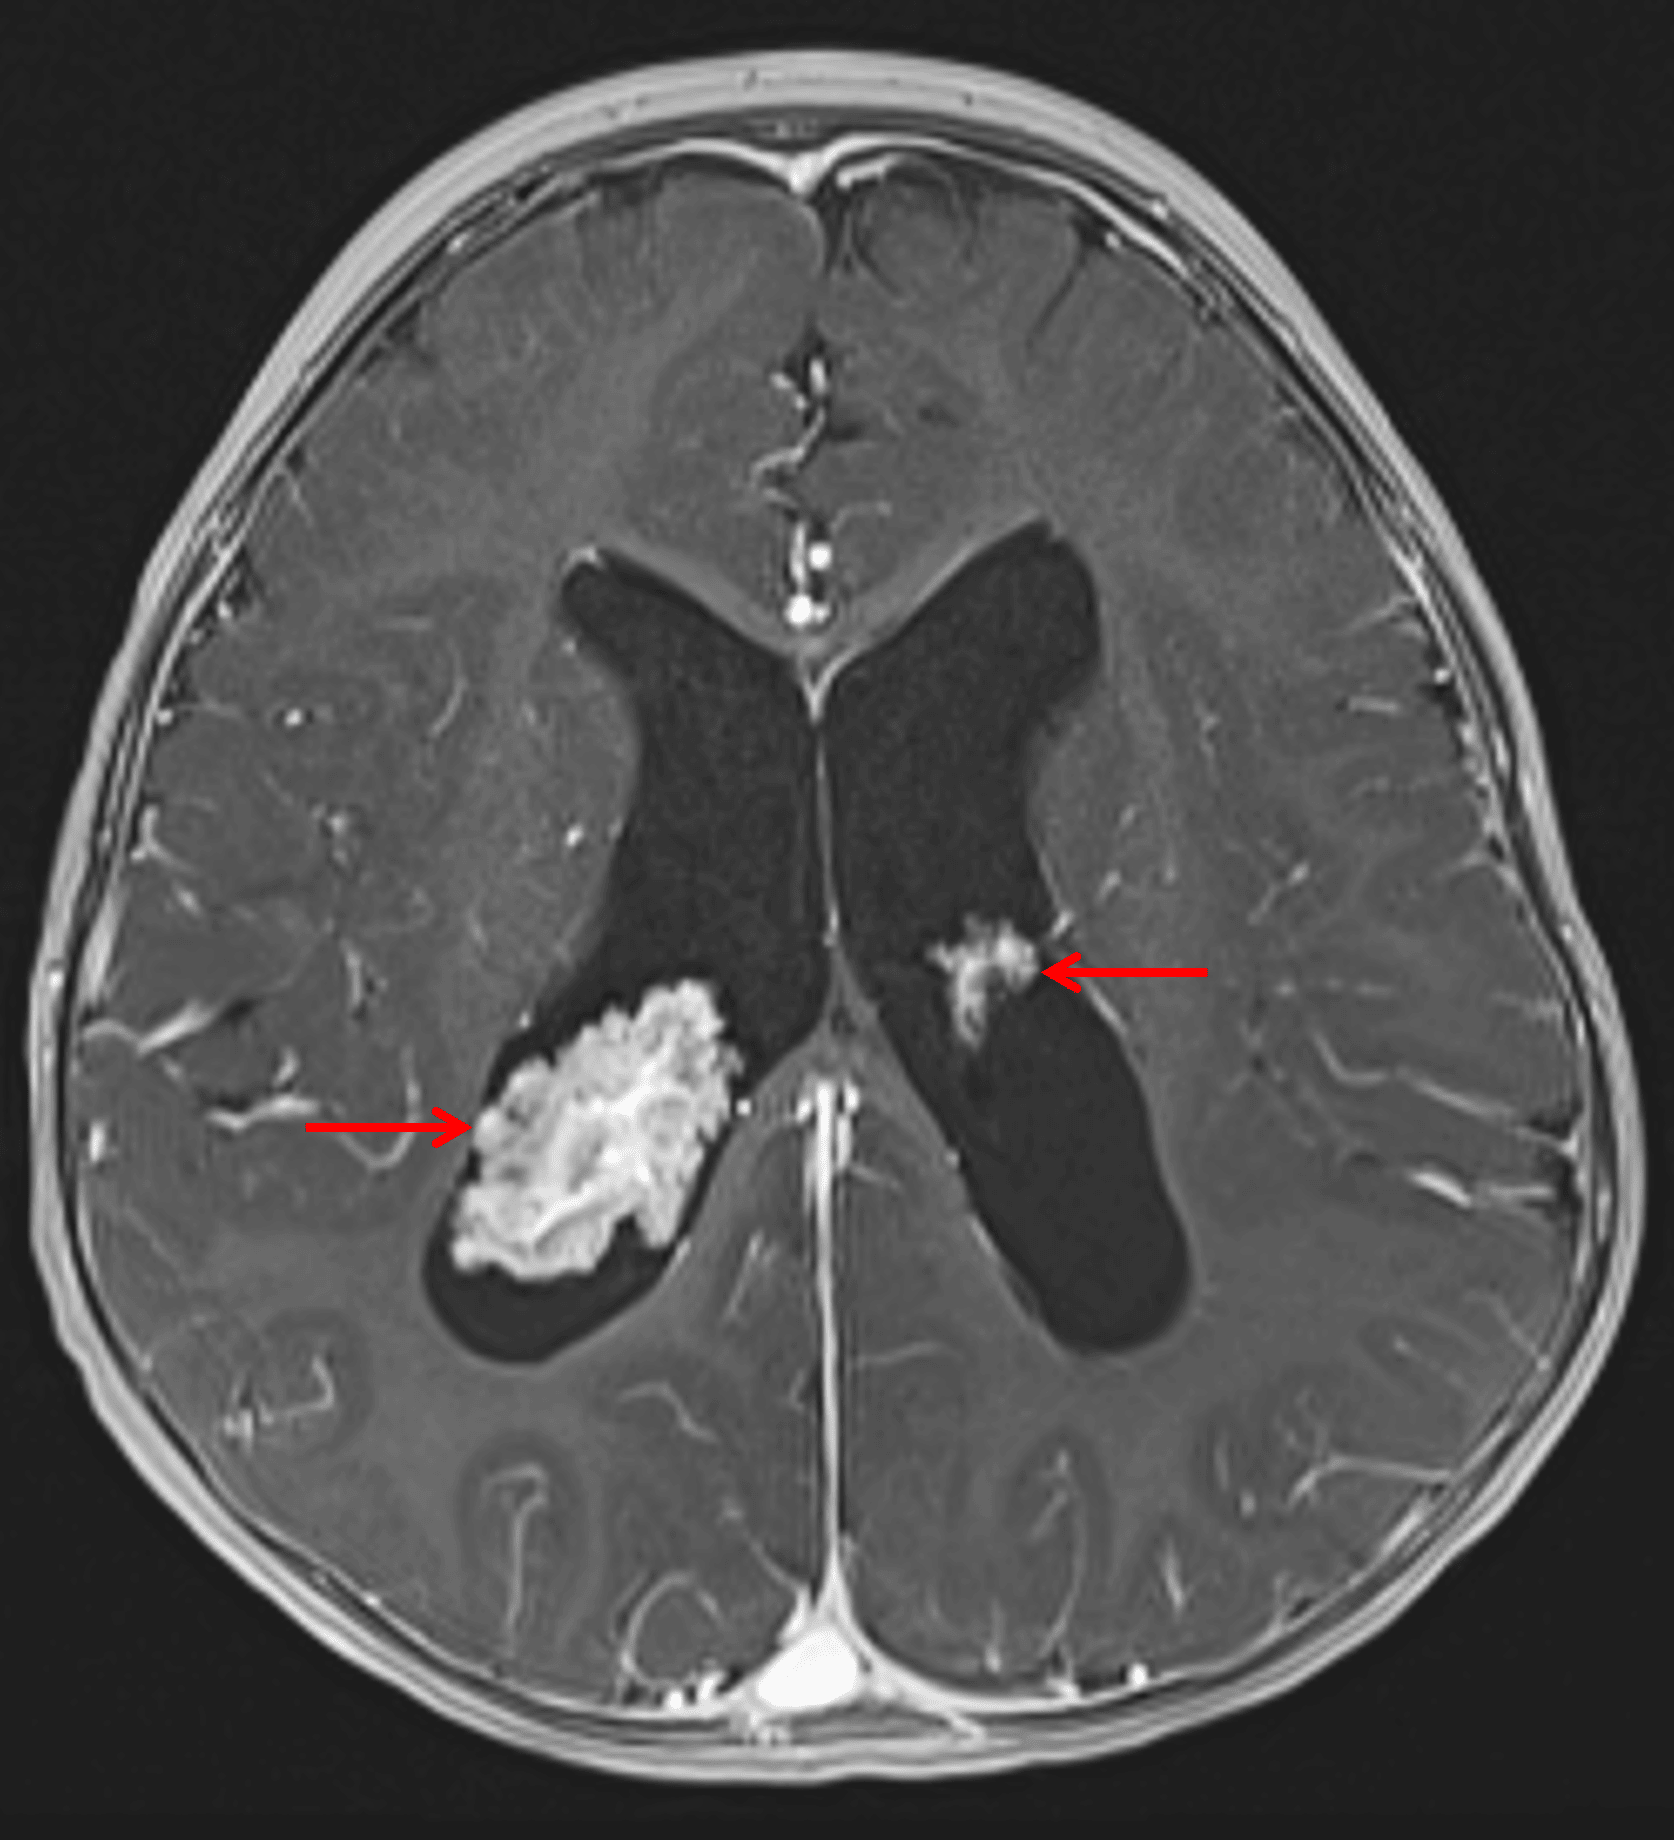

• Frondlike avidly enhancing lesions in the bilateral lateral ventricles associated with the choroid plexus

• The right lateral ventricular lesion is larger and measures 3.2 x 2 x 3.5 cm

• These lesions are isointense on T1 and T2 and do not demonstrate corresponding susceptibility artifact or restricted diffusion

Enlargement of the right greater than left choroid plexus in the lateral ventricles (red arrows).